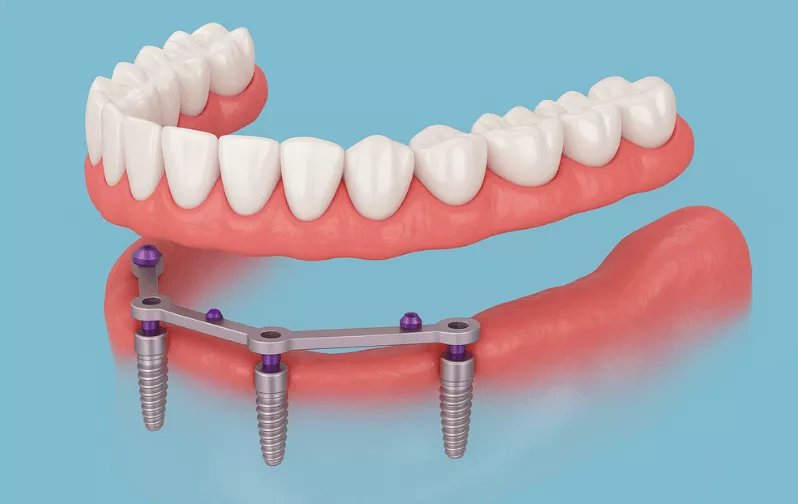

Los implantes dentales All-on-4 consisten en la colocación estratégica de cuatro implantes dentales en cada arco (superior o inferior), sobre los cuales se coloca un puente completo de dientes fijos.

Esta técnica permite reemplazar todos los dientes perdidos de un arco de manera estable, funcional y estética, utilizando menos implantes que los métodos tradicionales.

Los implantes All-on-4 representan una excelente opción para pacientes que buscan restaurar completamente su función masticatoria y apariencia estética.